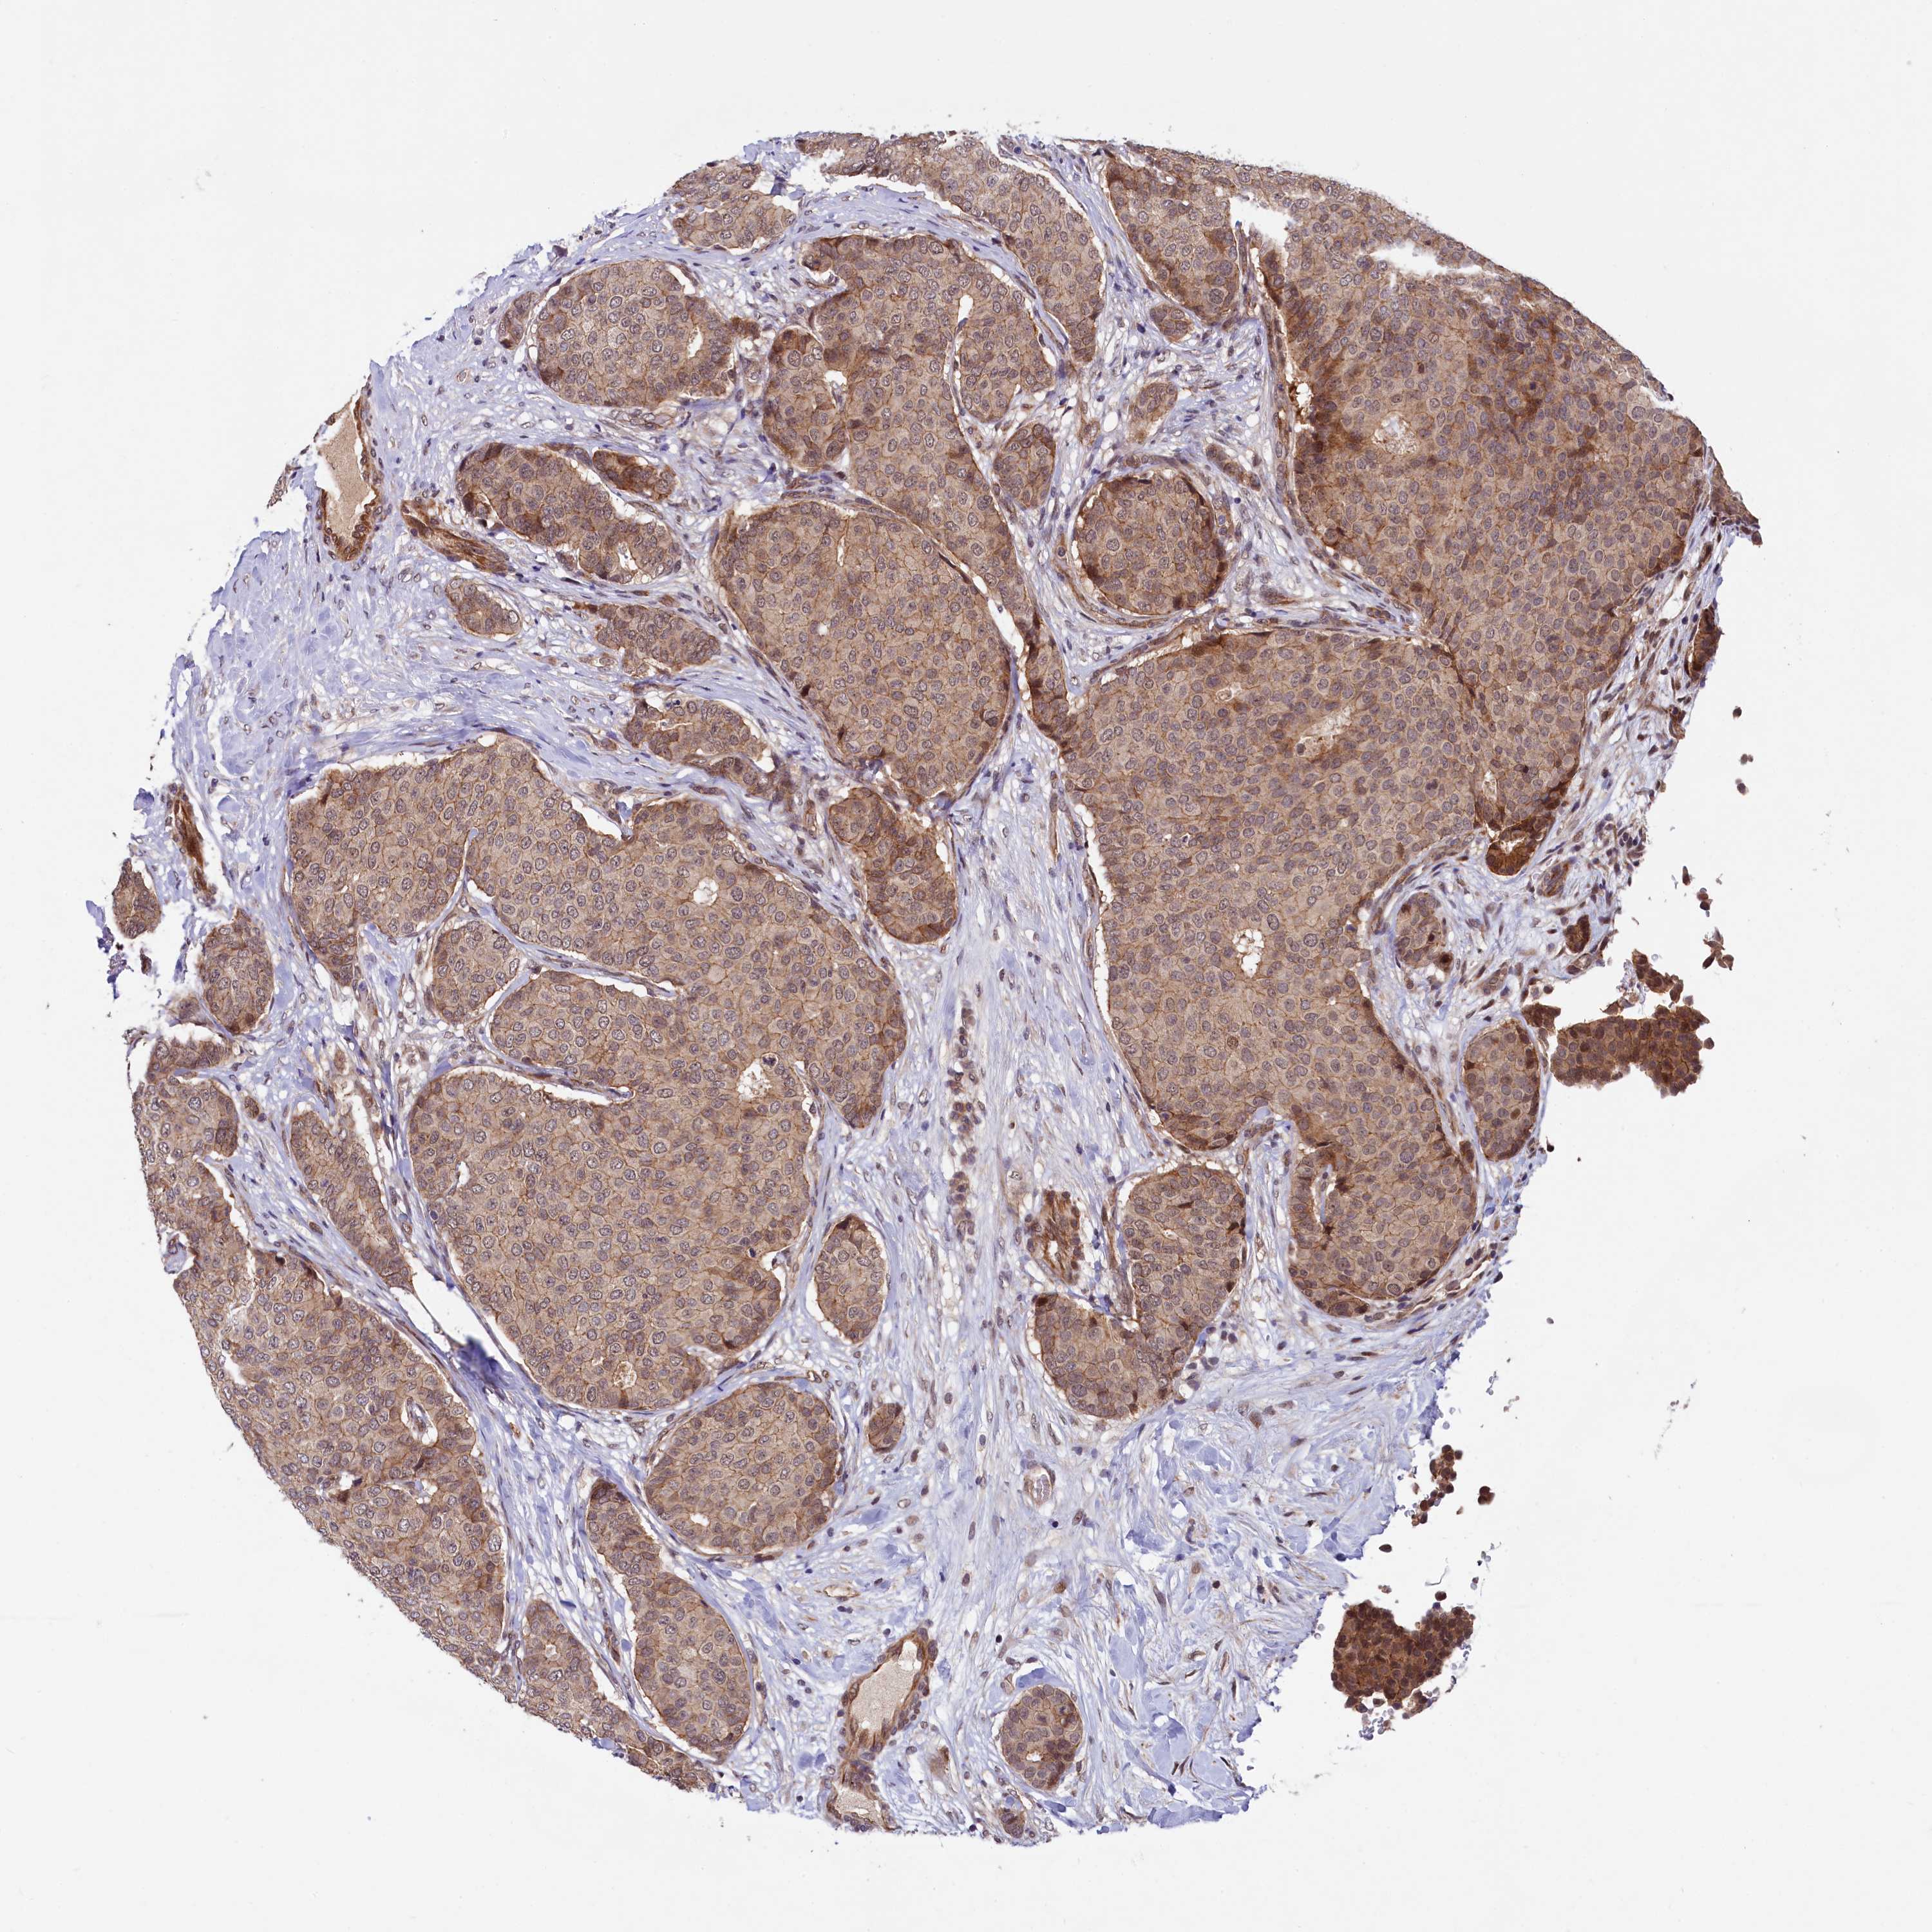

CANCER BREAST CANCER Show tissue menu

BRCA TCGA BRCA VALIDATION PROTEIN EXPRESSION